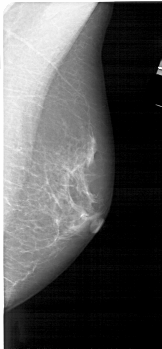

A_1545_1.RIGHT_CC

RIGHT_CC LINES 5131 PIXELS_PER_LINE 2266 BITS_PER_PIXEL 12 RESOLUTION 43.5 NON_OVERLAY